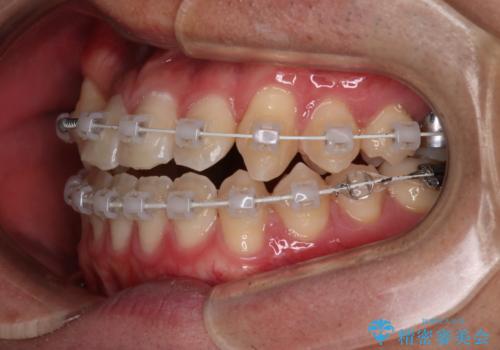

- 矯正装置

- 審美装置

その点を考慮して、リンガルアーチを用いて奥歯を遠心移動し、前歯にIPR(歯と歯の間を削る処置)を行うことでスペースを作って歯並びを整えていく計画を立てました。

リンガルアーチを用いて奥歯を遠心移動し、前歯にIPR(歯と歯の間を削る処置)を行うことでスペースを作って歯並びを整えていく計画を立てました。